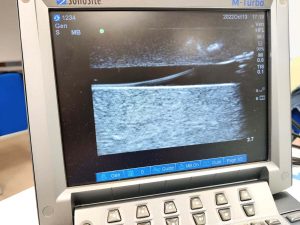

La punció ecoguiada, una tècnica gens invasiva que permet a la infermera veure, de forma clara i directa, l’estructura vascular a la qual ha d’accedir i col·locar l’agulla en el lloc més adient, evitant incomoditats i complicacions per al pacient.

El cicle programat de forma itinerant pel COILL ha tingut una molt bona acollida entre les infermeres de la província que han pogut profunditzar en la punció ecoguiada, una tècnica gens invasiva que permet a la infermera veure, de forma clara i directa, l’estructura vascular a la qual ha d’accedir i col·locar l’agulla en el lloc més adient per inserir la via (catèter) o qualsevol altre dispositiu d’accés vascular (DAV), evitant incomoditats i complicacions per al pacient.